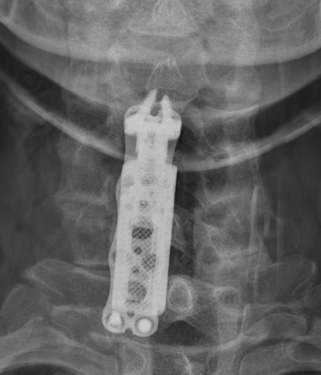

ACDF versus corpectomy

- multilevel ACDF versus anterior cervical corpectomy and fusion

- meta-analysis of 8 studies and 878 patients

- ACDF had better postoperative angles and fusion rates, and reduced blood loss and complications